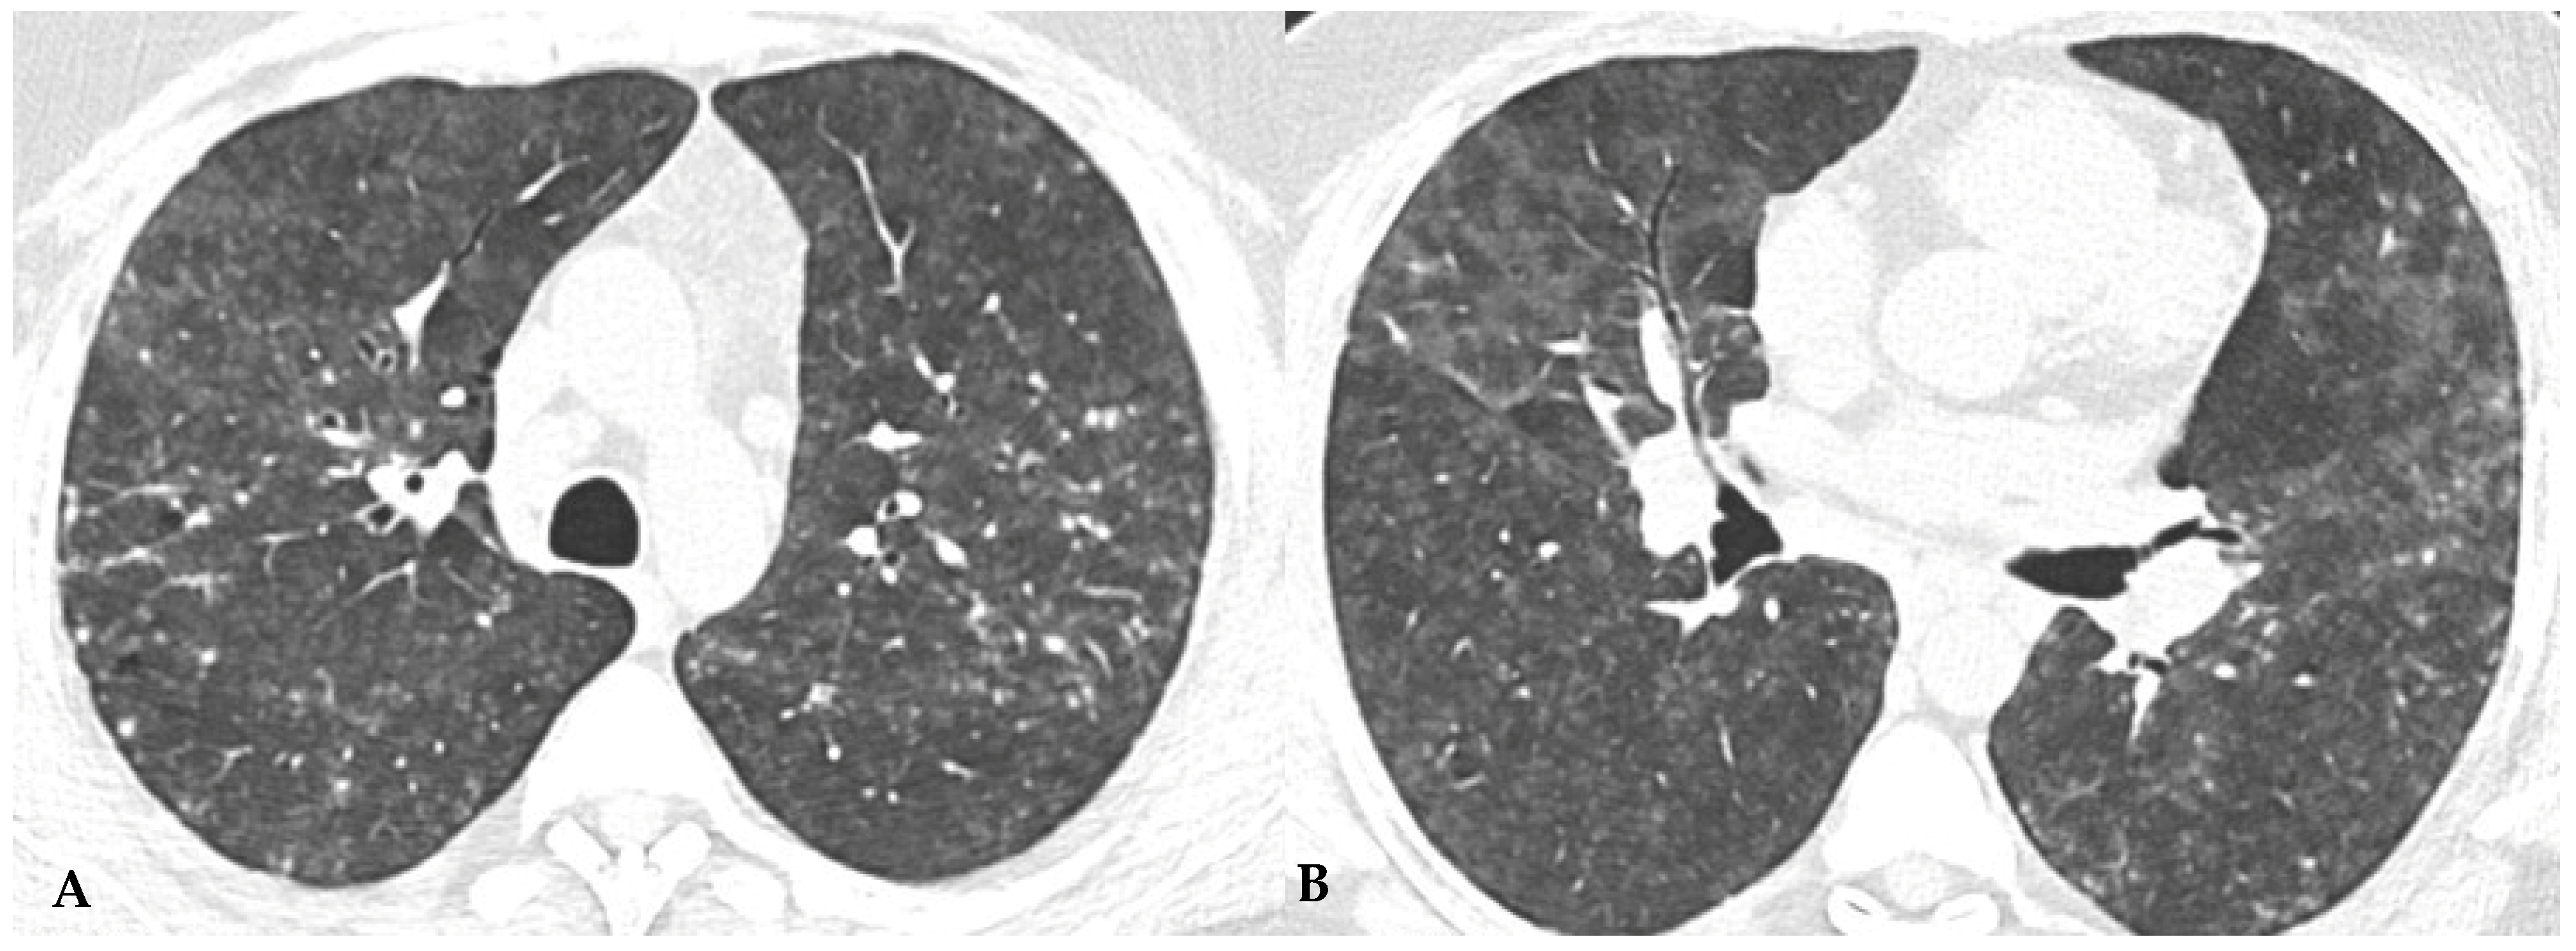

Figure 6.

HRCT of the chest and magnification areas of RLL and LUL in FHP. Three-density pattern with lobular areas of reduced attenuation in both lungs (magnification images), overlapping with areas of increased density where distinct fibrotic alterations are evident, characterized by intra- and inter-lobular thickening with traction bronchiectasis and bronchiolectasis (red box). In certain patients, the absence of typical HRCT fibrotic features leads to their classification as “pattern compatible with FHP”. Suggestive elements of this pattern are fibrosis with a mixed central and peripheral distribution (Figure 7) and the fibrotic pattern with basal predominance (Figure 8).

Figure 7.

FHP with small areas of GGO related to acute exacerbation: axial chest HRCT scan. HRCT pattern characterized by mild amorphous GGO components in the upper lobes (red box), predominantly centrally located, with sectoral signs of interface and anterior asymmetric reticulations. Minimal traction bronchiolectasis coexists (A); subcarinal scan reveals GGO with moderate distortion, septal thickening and alterations predominantly bronchocentric in distribution (green box in (B)). The changes exhibit a “patchy” distribution with areas of mosaic attenuation.